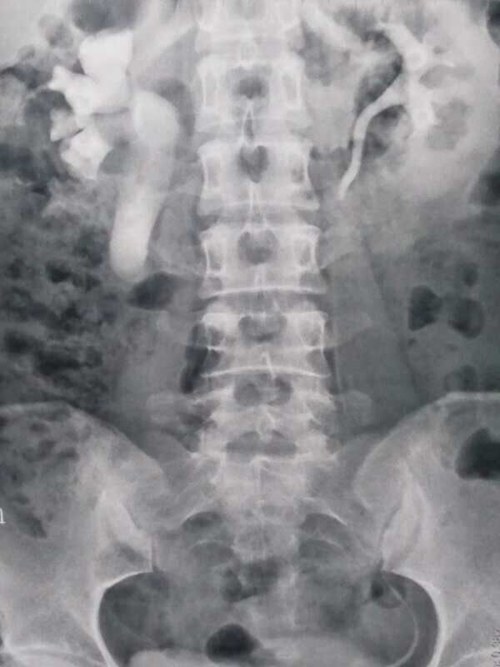

术前静脉肾盂造影

该例手术的顺利完成,积累了此类病例的诊疗经验,提升了疑难危重疾病的诊断和治疗水平。